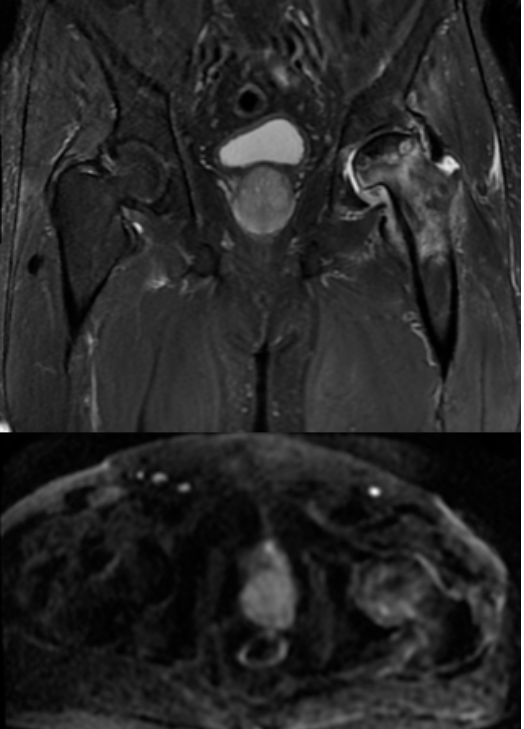

MRI结果显示,王先生的左侧股骨头已经变扁,出现局部塌陷。

左侧股骨头变扁,局部塌陷,骨质内见线状T1WI低信号,髋臼及股骨近端骨松质见片状T1WI低、T2WI压脂高信号,DWI高信号,周围滑膜增厚,邻近软组织肿胀,PD压脂信号增高,关节腔少量积液。

在这个病例中,磁共振(MRI)发挥了无可替代的作用。与X光片只能显示骨骼形态、CT主要显示骨质结构不同,MRI的突出优势在于:

多序列、多参数成像:如同本例中运用的T1WI、T2WI压脂、DWI、PD压脂等不同序列,能从血流、水分、细胞密度等多个维度评估病变性质,为医生提供全面的诊断信息。